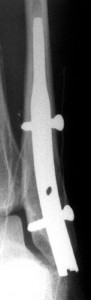

It is suitable for treatment of distal fibula fractures. After surgery the limb can be loaded immediately, it has a high patient-satisfaction index.

Main characteristics and advantages: